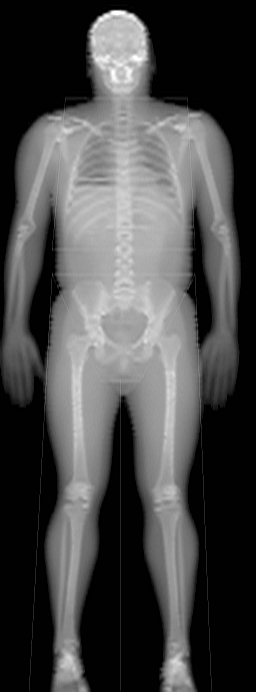

Norland utilizes automated technology to deliver efficient workflow and accurate studies without methodological error.

- Automatic ROI setting eliminates operator intervention.

- Intelligent edge detection streamlines post scan analysis.

- Norland's unique Dynamic Filtration process ensures minimal subject radiation dose by adjusting X-ray flux based on tissue thickness.

- Norland systems eliminate detectable beam scatter allowing shortest operating distance in the industry.